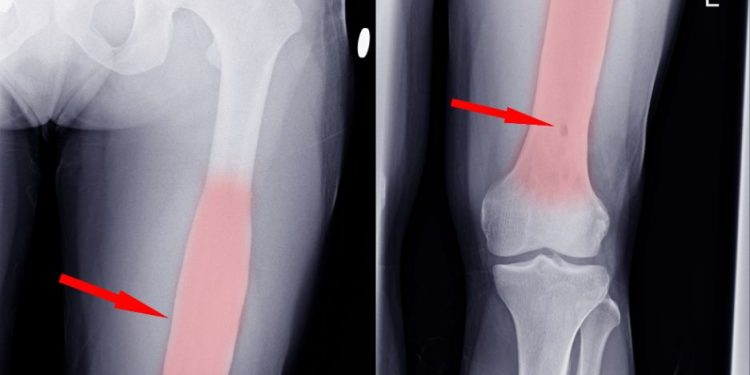

Among the most common osteosarcoma symptoms are swelling, pain, and bone fracture. The symptoms of osteosarcoma may be similar to those of other health problems, so it is important to talk to a healthcare provider to determine what symptoms you may have. You may also have other tests or imaging tests, such as a bone scan, to determine if you have osteosarcoma.

The symptoms of osteosarcoma may start as a pain in the bone, or it may appear as a lump or swelling. You may also experience a limp or pain when you walk or lift something. This pain may worsen during activity or at night. If you have any pain in the bones, you should see your doctor immediately.

Osteosarcoma treatment depends on the stage of the disease. If you have a high grade tumor, it is more likely to spread to other parts of the body. The symptoms of high grade tumors can be very severe, including pain and fractures in the bone around the tumor.